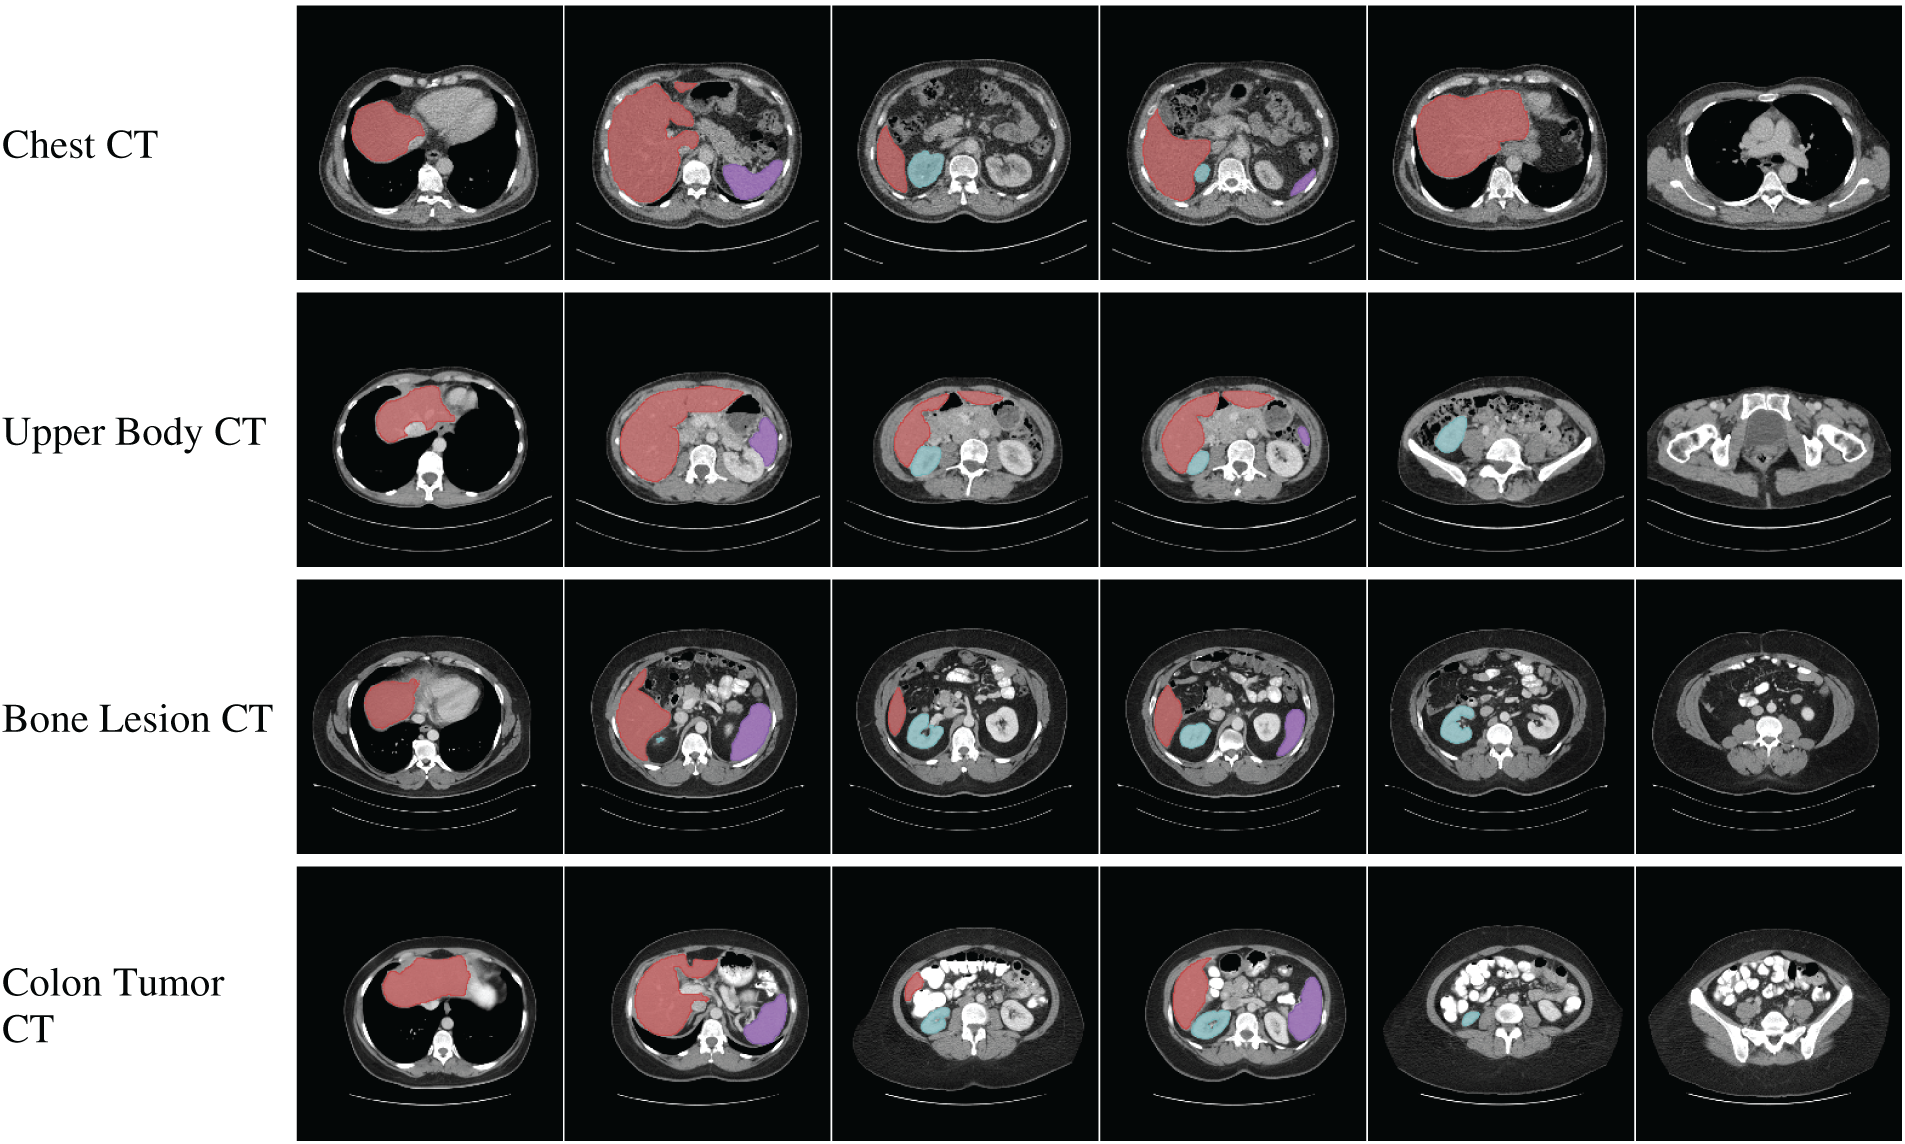

Collaborations among clinical, academic, and industry stakeholders play a pivotal role in advancing innovation within the medical imaging field. High-profile computer vision challenges, such as KUMAR [113], CHAOS [114], CVC-ClinicDC [115], and MonuSeg [113], that provide monetary incentives for competitive analysis on standardized datasets are accelerating large-scale benchmarking and spurring algorithmic innovation. In parallel, universities and hospitals are increasingly releasing annotated datasets across various organ systems to support research efficiency and foster progress in the field. The growing availability of multi-organ datasets derived from clinical imaging modalities like CT, MRI, and ultrasound significantly reduces the barriers to entry for clinically relevant tasks such as tumor segmentation, e.g., BRATS [116], GlaS [117], BUSI [118], and disease classification, e.g., ADNI [119], Sample result images from CT datasets, i.e., MICCAI 2021 FLARE Challenge Dataset [120], etc., based on VISTA-3D [121] are presented in Fig. 4, illustrating the diversity of abdominal organ structures and variations across different CT scans used in the challenge. By minimizing the need for individual research groups to independently curate data, these shared resources enable more rapid and reproducible experimentation. Further dataset details are provided in Table 4. As the importance of cross-dataset generalization grows for real-world clinical deployment, the demand for diverse, high-quality datasets is expected to increase accordingly.

Figure 4: Visualization of segmentation outputs from CT Datasets using VISTA-3D